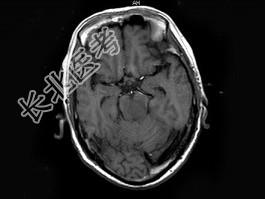

- 单项选择题男,70岁, 头痛,嗜睡伴癫痫发作2次, 行MRI平扫及增强扫描见颅内多发病灶,曾行放射治疗, 病灶明显缩小(此图为治疗前图),据此最可能的诊断为 ( )

A、颅内转移瘤

B、淋巴瘤

C、胶质瘤

D、血管瘤

E、未见异常